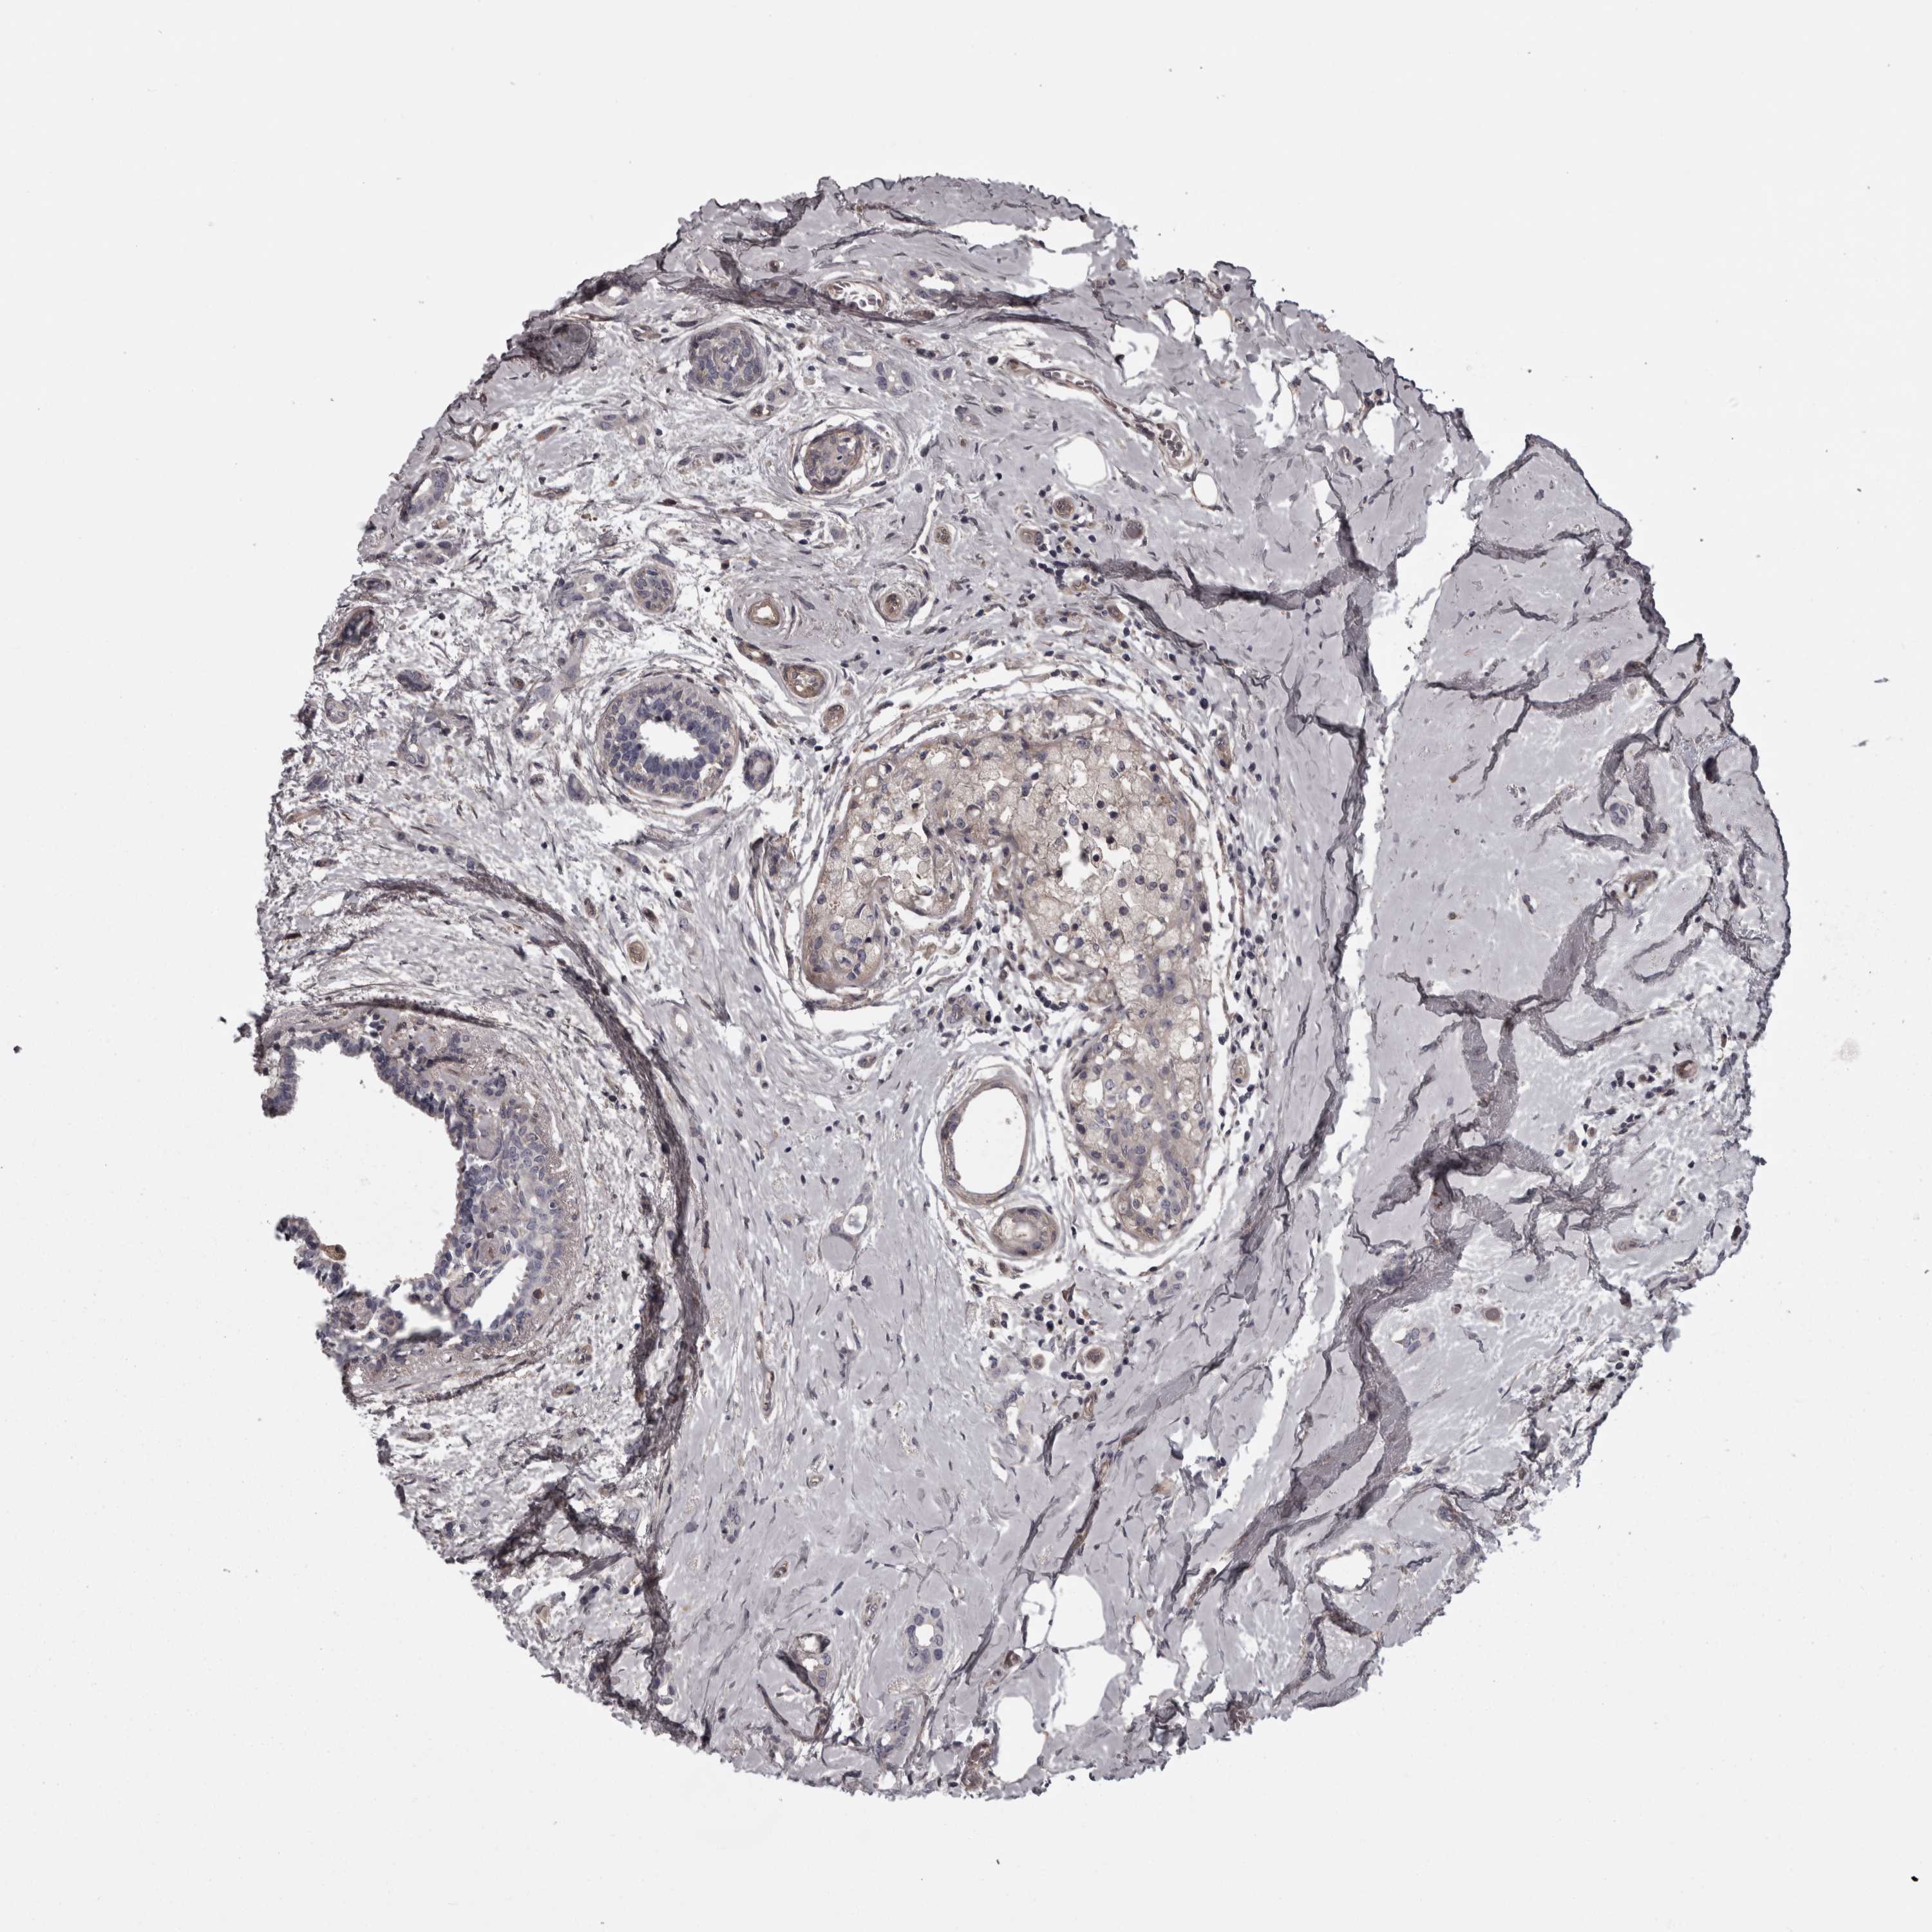

CANCER BREAST CANCER Show tissue menu

Breast cancer

Human cancer